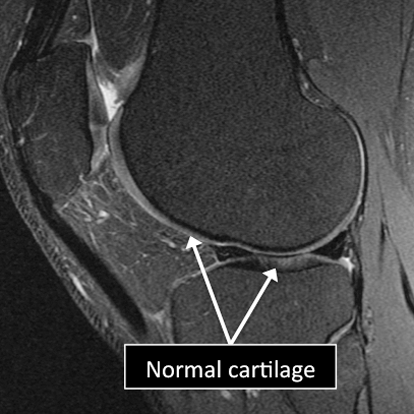

- MRI allows us to see different regions of the cartilage.

- Several injuries or diseases affecting the cartilage can be diagnosed using MRI.

- Common things affecting the cartilage include degenerative or traumatic defects, abnormal calcium deposition in the cartilage, fractures affecting the cartilage and the underlying bone (osteochondral fractures), among others.

Knee MRI examinations showing normal (top) and abnormal (bottom) articular cartilage.